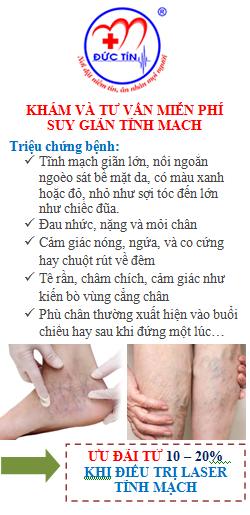

KhuyẾn cáo vỀ hiỆu quẢ và tính an toàn cỦa VADs.

Trong bản khuyến cáo hiện hành, những hướng dẫn về việc sử dụng hệ thống phân loại GRADE làm cơ sở cho việc điều trị bằng VADs. Những khuyến cáo này bắt nguồn từ khuyến cáo trước đó của Perrin và Ramellet,

Liệu pháp xơ hóalà tiêm hay truyền một chất gây xơ hóa vào tĩnh mạch trào ngược để phá hủy nội mô và sợi hóa mạch máu. Tiêm trực tiếp chất gây xơ vào tĩnh mạch thường dành cho các tổn thương mao mạch (telangiectatic lesions) hơn là CVI. Gây độc tĩnh mạch (phlebotonics) chưa được chứng minh có ích trong điều trị suy tĩnh mạch mạn tính.

Suy tĩnh mạch không phải là không phổ biến hay không lành tính. Điều trị nhằm giảm triệu chứng và điều chỉnh các nguyên nhân nền nếu có

HƯỚNG DẪN BỆNH NHÂN

Hướng dẫn mang vớ áp lực thường xuyên, liên tục cho bệnh nhân CVI, trừ khi họ không dung nạp được, hoặc không thể mang vớ áp lực vì một lí do nào đó.

Tránh đứng hay ngồi lâu.